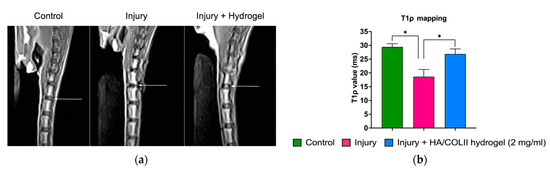

We employed MRI to assess the hydration status in the IVD. The T1ρ mapping of the MRI was higher in the control, which reflects the hydrophilicity of the ECM composition in the IVD. However, it was decreased in the untreated injury group. We observed a higher T1ρ value in rats treated with hydrogel, suggesting that hydrogel restores disc hydration (Figure 5).

Figure 5. The MRI analysis for disc hydration. (a) A representation of MRI images on T1ρ mapping. The arrow indicates the intervertebral discs of control, injury and treatment, respectively. (b) The histogram shows that the T1ρ value of the hydrogel-treated injury group was higher compared to the non-treated injury group. Data are means ± SEM, n = 3. * p < 0.05 constitutes a significant difference between groups, determined by one-way ANOVA and Bonferroni’s post hoc test.

The initiation of IVD degeneration started when there was an extensive reduction of vacuolated notochordal cells in the NP [2]. During IVD maturation, the larger notochordal cells undergo morphology changes and functional shifts to smaller fibrochondrocyte-like cells. The reduction of notochordal cells during ageing contributes to matrix changes and decreases the cellularity of the NP [2,21]. This leads to the alteration and degradation of the ECM content. Using MRI, we analysed the T1ρ mapping, which reflects the proteoglycan deposition in the IVD. Proteoglycan molecules have a high affinity for water due to their negative charges, which attract and bind water molecules, mainly to maintain disc hydration. Herein, we observed a decrease of increase in disc hydration following disc injury. The hydrogel-treated group showed increased hydration, suggesting the HA/COLII hydrogel promotes tissue repair. This is consistent with the previous study, which demonstrated that HA hydrogel increases the expression of type II collagen and aggrecan in the NP [22].